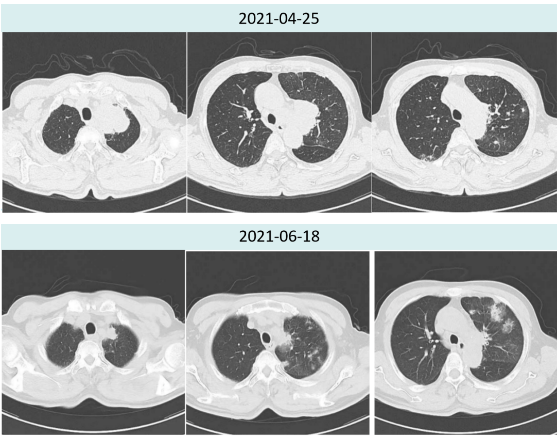

2021年4月25日胸部CT提示:左上肺占位,左肺?增?,考虑左上肺癌伴左肺?及纵隔淋巴结转移,两肺散在炎症,左肺上叶部分实变。左肺下叶磨玻璃结节。

2021年6月18日治疗两周期后复查胸部CT提示:肿瘤较前明显缩小(4.5cm→2.0cm),新增多发炎性病灶,总体疗效评价为PR。

图1.患者治疗前后胸部病灶对比

图2.患者治疗前后肺炎情况对比